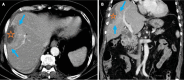

Endoscopic retrograde cholangiopancreatography (ERCP) is a cornerstone procedure for the diagnosis and management of pancreatic and hepatobiliary diseases. Although its diagnostic role has been increasingly supplanted by noninvasive imaging modalities such as magnetic resonance imaging (MRI) and magnetic resonance cholangiopancreatography, the therapeutic applications of ERCP have continued to expand. ERCP is widely used and has a generally favorable safety profile. However, it is important to recognize expected post-procedural imaging findings and serious complications that can arise. The increasing complexity of therapeutic interventions and the growing volume of procedures have led to a higher incidence of complications that often present with overlapping clinical and laboratory features, underscoring the critical role of imaging in differential diagnosis. This review focused on the typical normal ERCP findings and the imaging characteristics of common complications, including pancreatitis, bleeding, ERCP-related infections, perforations, and stent-related complications. Computed tomography (CT) is particularly valuable in timely recognition, management, and surgical decision-making for these complications. Furthermore, MRI offers a radiation-free alternative for managing complications in selected patients. Therefore, radiological modalities, particularly CT and MRI, are critical tools for the rapid diagnosis, management, and surgical decision-making processes for post-ERCP complications.